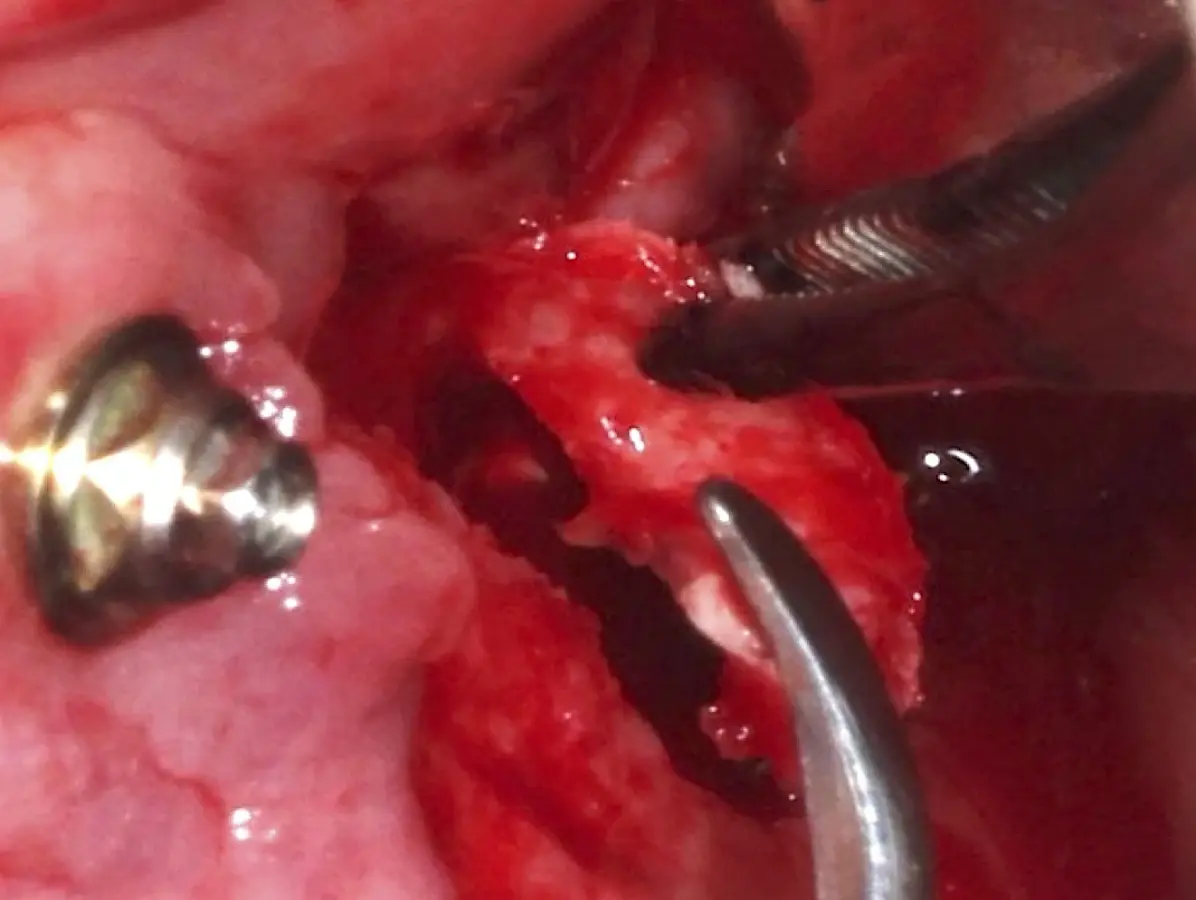

La técnica se inicia con la colocación de anestesia infiltrativa, posteriormente se realiza una incisión crestal o paracrestal con posibles liberantes verticales que deben de estar alejadas por lo menos 5 mm de los límites de la futura ventana y sobrepasar la línea mucogingival. Se realiza una elevación de colgajo, se inicia la antrostomía y antroplastía. Para ello, se emplea el inserto redondo diamantado de corte al momento de delimitar los bordes de la ventana de acceso. Luego se cambia al inserto aserrado liso de calibre fino con superficie diamantada, para profundizar y eliminar el hueso en el contorno de la ventana. Una vez que se traslucen los tejidos, se puede optar por el retiro de la tapa ósea o el levantamiento de ésta junto con la membrana.

Se inicia la elevación de la membrana de Schneider con el inserto redondeado no cortante en forma de disco, empleando movimientos suaves. El levantamiento puede complementarse con elevadores convencionales, siguiendo la dirección mesiodistal. La fase de desprendimiento inicia con el piso y sigue hacia la pared mesial para terminar, y de ser necesario, hacia la pared posterior. Existen diversos insertos con angulaciones y longitudes para mayor accesibilidad16 (Figura 1).

El clínico puede retirar la tabla ósea o introducirla como “tienda de campaña” dentro del seno maxilar. En cualquiera de las alternativas, es importante evaluar la presencia de tabiques óseos y de la arteria postero alveolar superior.